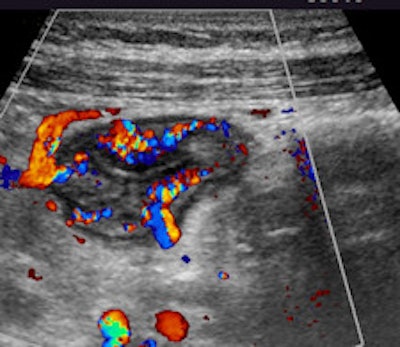

Cross-sectional (left) and longitudinal (right) images of the terminal ileum show thickened bowel wall and inflammatory echogenic fat in a young female patient with acute Crohn's disease of the terminal ileum. All images courtesy of Dr. Stephanie Wilson.

Additional color Doppler images show hyperermia of the bowel.

Additional color Doppler images show hyperermia of the bowel.When performing ultrasound of the gastrointestinal tract, there are technical and patient-related challenges. The technical demands include equipment requirements for a broad range of transducer frequencies to allow for scanning of the bowel within the focal range of the transducer so that exceptionally high resolution can be achieved. Although all ultrasound machines have low-frequency probes available, it is the addition of high-frequency probes, both linear and convex, which allows for good bowel assessment, especially in thin patients.